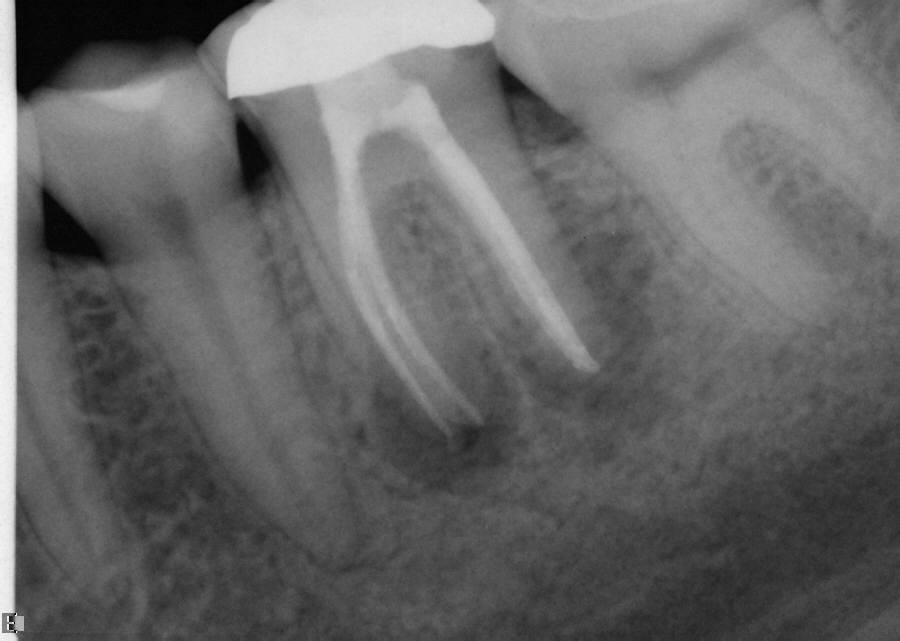

The master cone PA is the last indicator clinicians have in assessing whether or not their working lengths were truly accurate. This radiograph is crucial in affording the practitioner the opportunity to make adjustments to properly complete the procedure to the desirable lengths. An example is presented in Figure 15 through Figure 18. Figure 16 and Figure 17 show a master cone PA that demonstrates two of four canals to proper length. After adjusting the length of the other two master cones, the clinician was able to correct the lengths to produce a more appropriate result, as seen in Figure 18.

Fig 18. Completed case shows how the lengths were corrected prior to final obturation to achieve an ideal result.

Figure 18

Fig 16. Mesial-lingual (ML) length looks to be precise, while distal-lingual (DL) looks to be slightly long.

Figure 16

Fig 17. Mesial-buccal (MB) length appears to be long, and distal-buccal (DB) has a kink likely due to its joining the DL canal just before the apex.

Figure 17